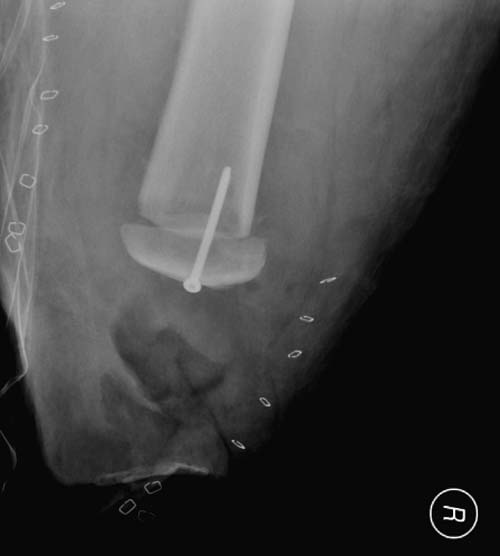

Большое спасибо всем Вам за помощь! Вчера прооперировали пациентку. Выполнили закрытую репозицию левой половины таза на тракционном столе под контролем ЭОП, закрытая фиксация левого КПС двумя каннулированными винтами. Учитывая удовлетворительное стояние отломков лонной и седалищной костей справа, а так же удовлетворительную ширину лона передние отделы стабилизировали системой ЦИТО

Послеоперационные КТ прилагаются

Винты введены в S1

Вроде бы все удалось. хорошо, что фрагмент (как выяснилось из КТ оказался небольшим), но для оценки лучше выкладывать рентген в стандартных проекциях

Здесь снимки, которые показывают направление стержня, а также идею репозиции вытяжением. На рентгенопроницаемых столах имеется возможность установить дополнительную раму, где по желанию можно увеличить или уменьшить высоту угла вытяжения. Для репозиции таза больной в положение на спине, стержень для вытяжения остается во время операции. Система подойдет для тракции головки бедра из вертлужной впадины, и для этого стерильная веревка и Synthes Universal Chuck with T-Handle.

Двухстороннее повреждение крестца и травматическая ампутация бедра, где неопытной бригадой дежурантов установлен верхний наружный фиксатор для стабилизации. На третий день ревизия на более стабильный, и окончательная фиксация. Первые снимки после стабилизации таза, и другие, где показаны (параллельные) правильная установка на AIIS т.е на месте прикрепления прямой мышцы бедра. Ампутация закончена костно пластическим методом.